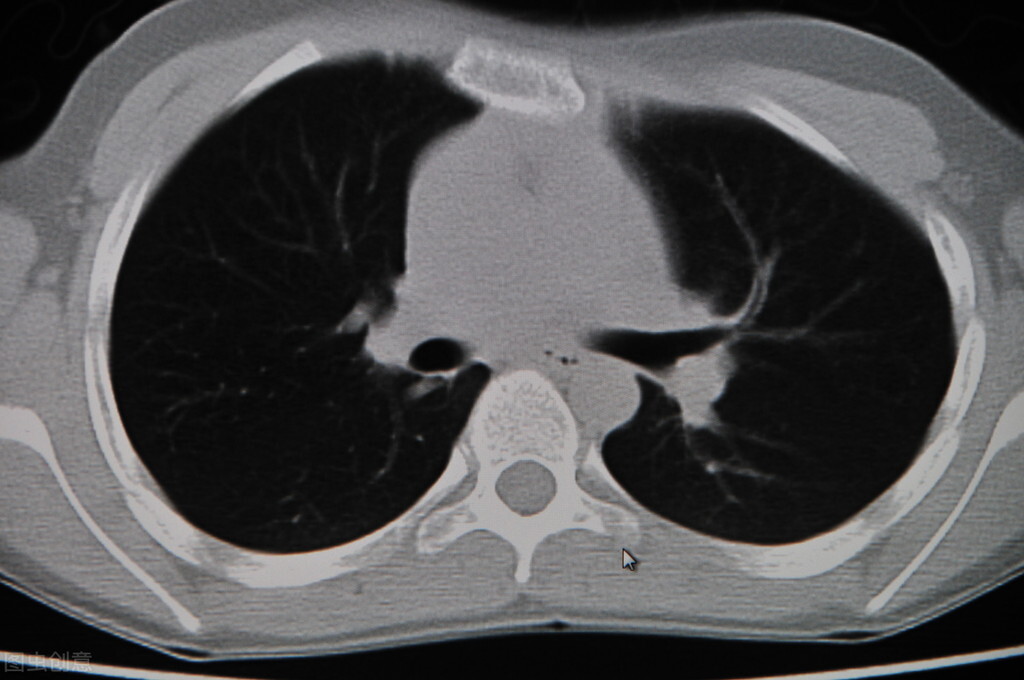

初诊,看了CT和检查报告显示他肺部的结节现在只有4毫米左右。有很大概率是良性的。